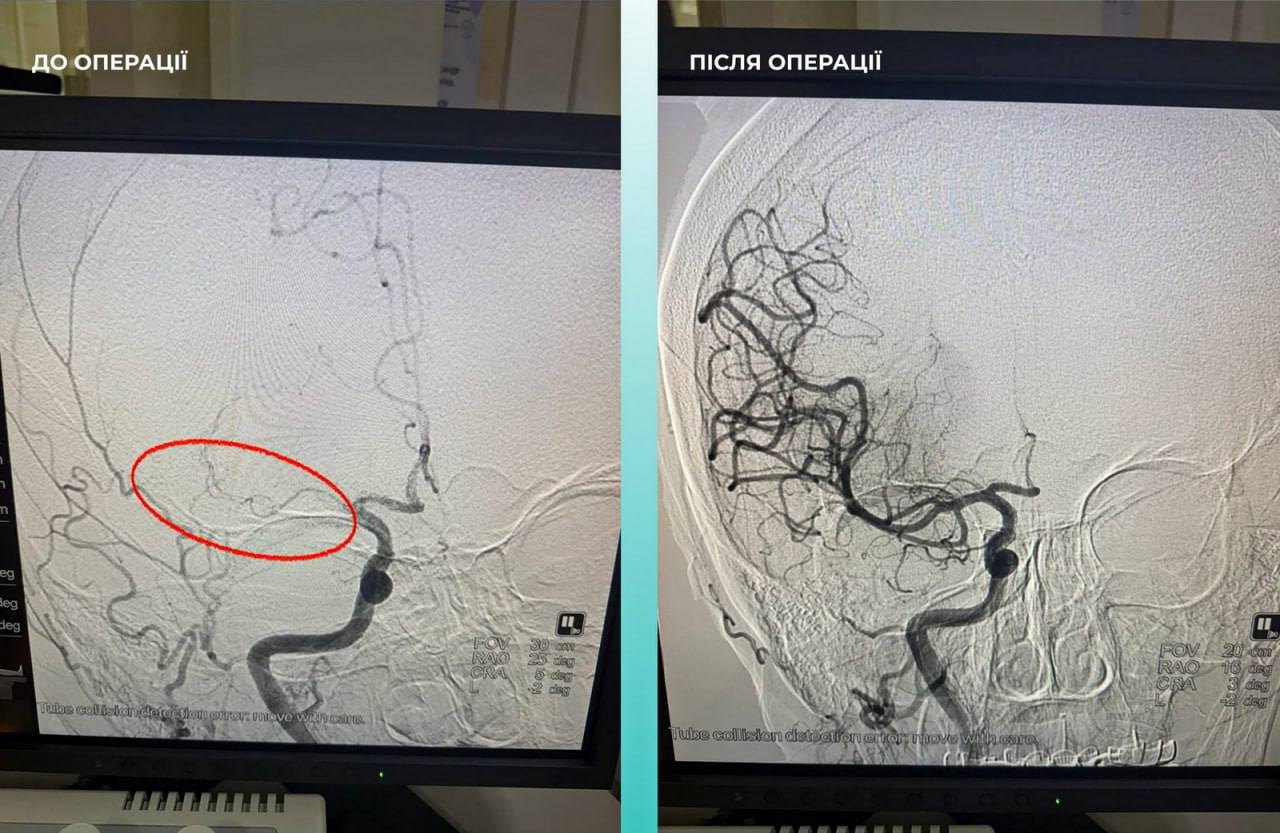

В больницу доставили женщину в тяжелом состоянии с признаками острого мозгового инсульта. Во время компьютерной томографии медики обнаружили окклюзию средней мозговой артерии. Кроме того, пациентка жаловалась на значительные затруднения с дыханием, что стало основанием для дополнительного обследования легких.

Дальнейшая диагностика подтвердила еще одно опасное осложнение — тромбоэмболию легочной артерии. Учитывая критическое состояние пациентки, мультидисциплинарная команда врачей приняла жизненно важное решение провести одновременную тромбэктомию из мозговой и легочной артерий.